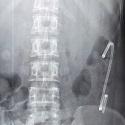

Complication rare du clou gamma: migration de vis cervicale au contact des vaisseaux iliaques

Younes Ouchrif, Issam Elouakili

PAMJ. 2014; 18: 188. Published 04 July 2014